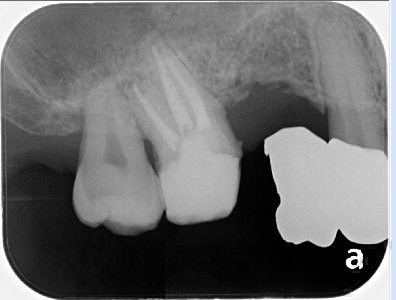

レントゲン上で左から2番目の歯の根管治療を行いました。

治療前は根の先に黒い像が確認できますが、治療後にはかなり縮小しているのが確認できました。